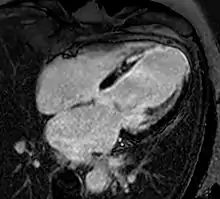

Atrial septal defect with dilation of the right ventricle by CMR

Enlarged right ventricle with poor function in a patient with repaired tetralogy of Fallot by CMR